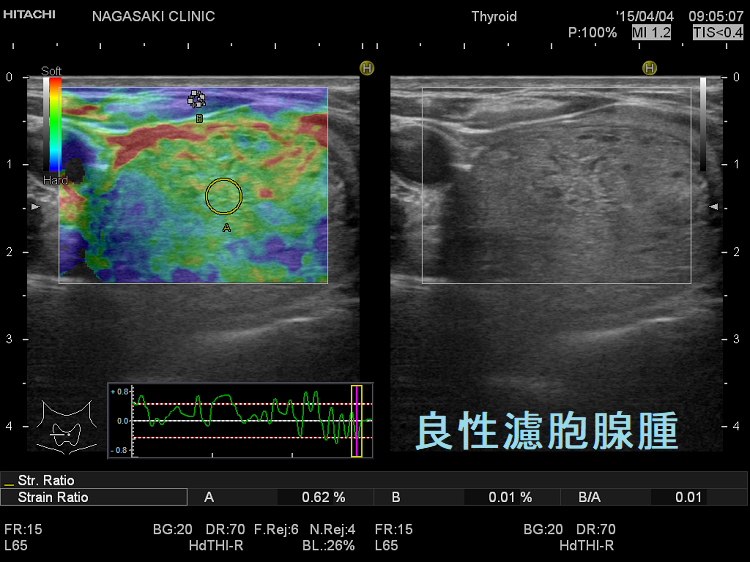

甲状腺良性濾胞腺腫腺腫様結節エラストグラフィー

甲状腺良性濾胞腺腫エラストグラフィー(JTEC パターン1)。甲状腺良性濾胞腺腫は、軟らかいために見えます。

甲状腺乳頭癌濾胞癌は特徴的なパターンで青くなります。

エラストグラフィー甲状腺濾胞癌良性濾胞腺腫と鑑別する判断材料になります。甲状腺濾胞癌は、穿刺細胞診で診断がほぼ不可能です(良性濾胞腺腫腺腫様結節と同じくクラス3にしかなりません)。甲状腺超音波(エコー)検査でも良性濾胞腺腫と鑑別するのは非常に困難ですが、甲状腺濾胞癌は、

5. エラストグラフィーで腫瘍周囲が青くなる(下左 JTEC パターン2)か、腫瘍全体が青く(JTEC パターン4)なります

同時に、ストレイン レイシォウ(strain ratio)≥1.7およびエコー上の悪性所見が1以上(OR=12.0、感度 75.0%、特異度 75.0%)(Endokrynol Pol. 2017;68(6):610-622.)。‎